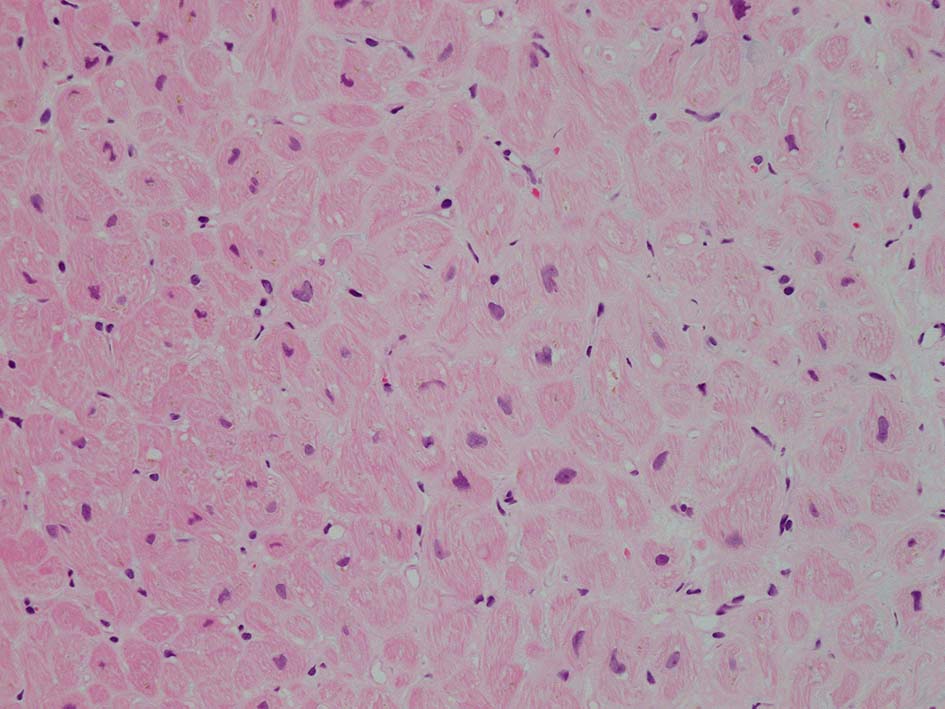

HE所見では, 明瞭な沈着物はわかりにくい. 血管壁が確認できる血管も少ない. congo-red染色で沈着が考えられる所見があり, 簡易偏光で(みずらいけれど)apple-greenの偏光があるように見える.(サムネイルのクリックで大きな画像が見られます)